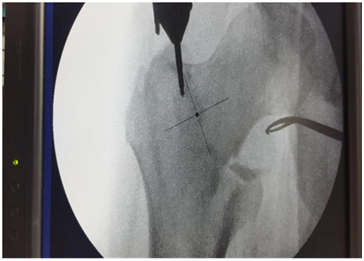

Entry point to be at tip with medial bias

In AP view entry point to be more medial. This allows 2 screws in head in good position (Figures 11&12).3

Figure 11 Entry point to be at tip with medial bias.